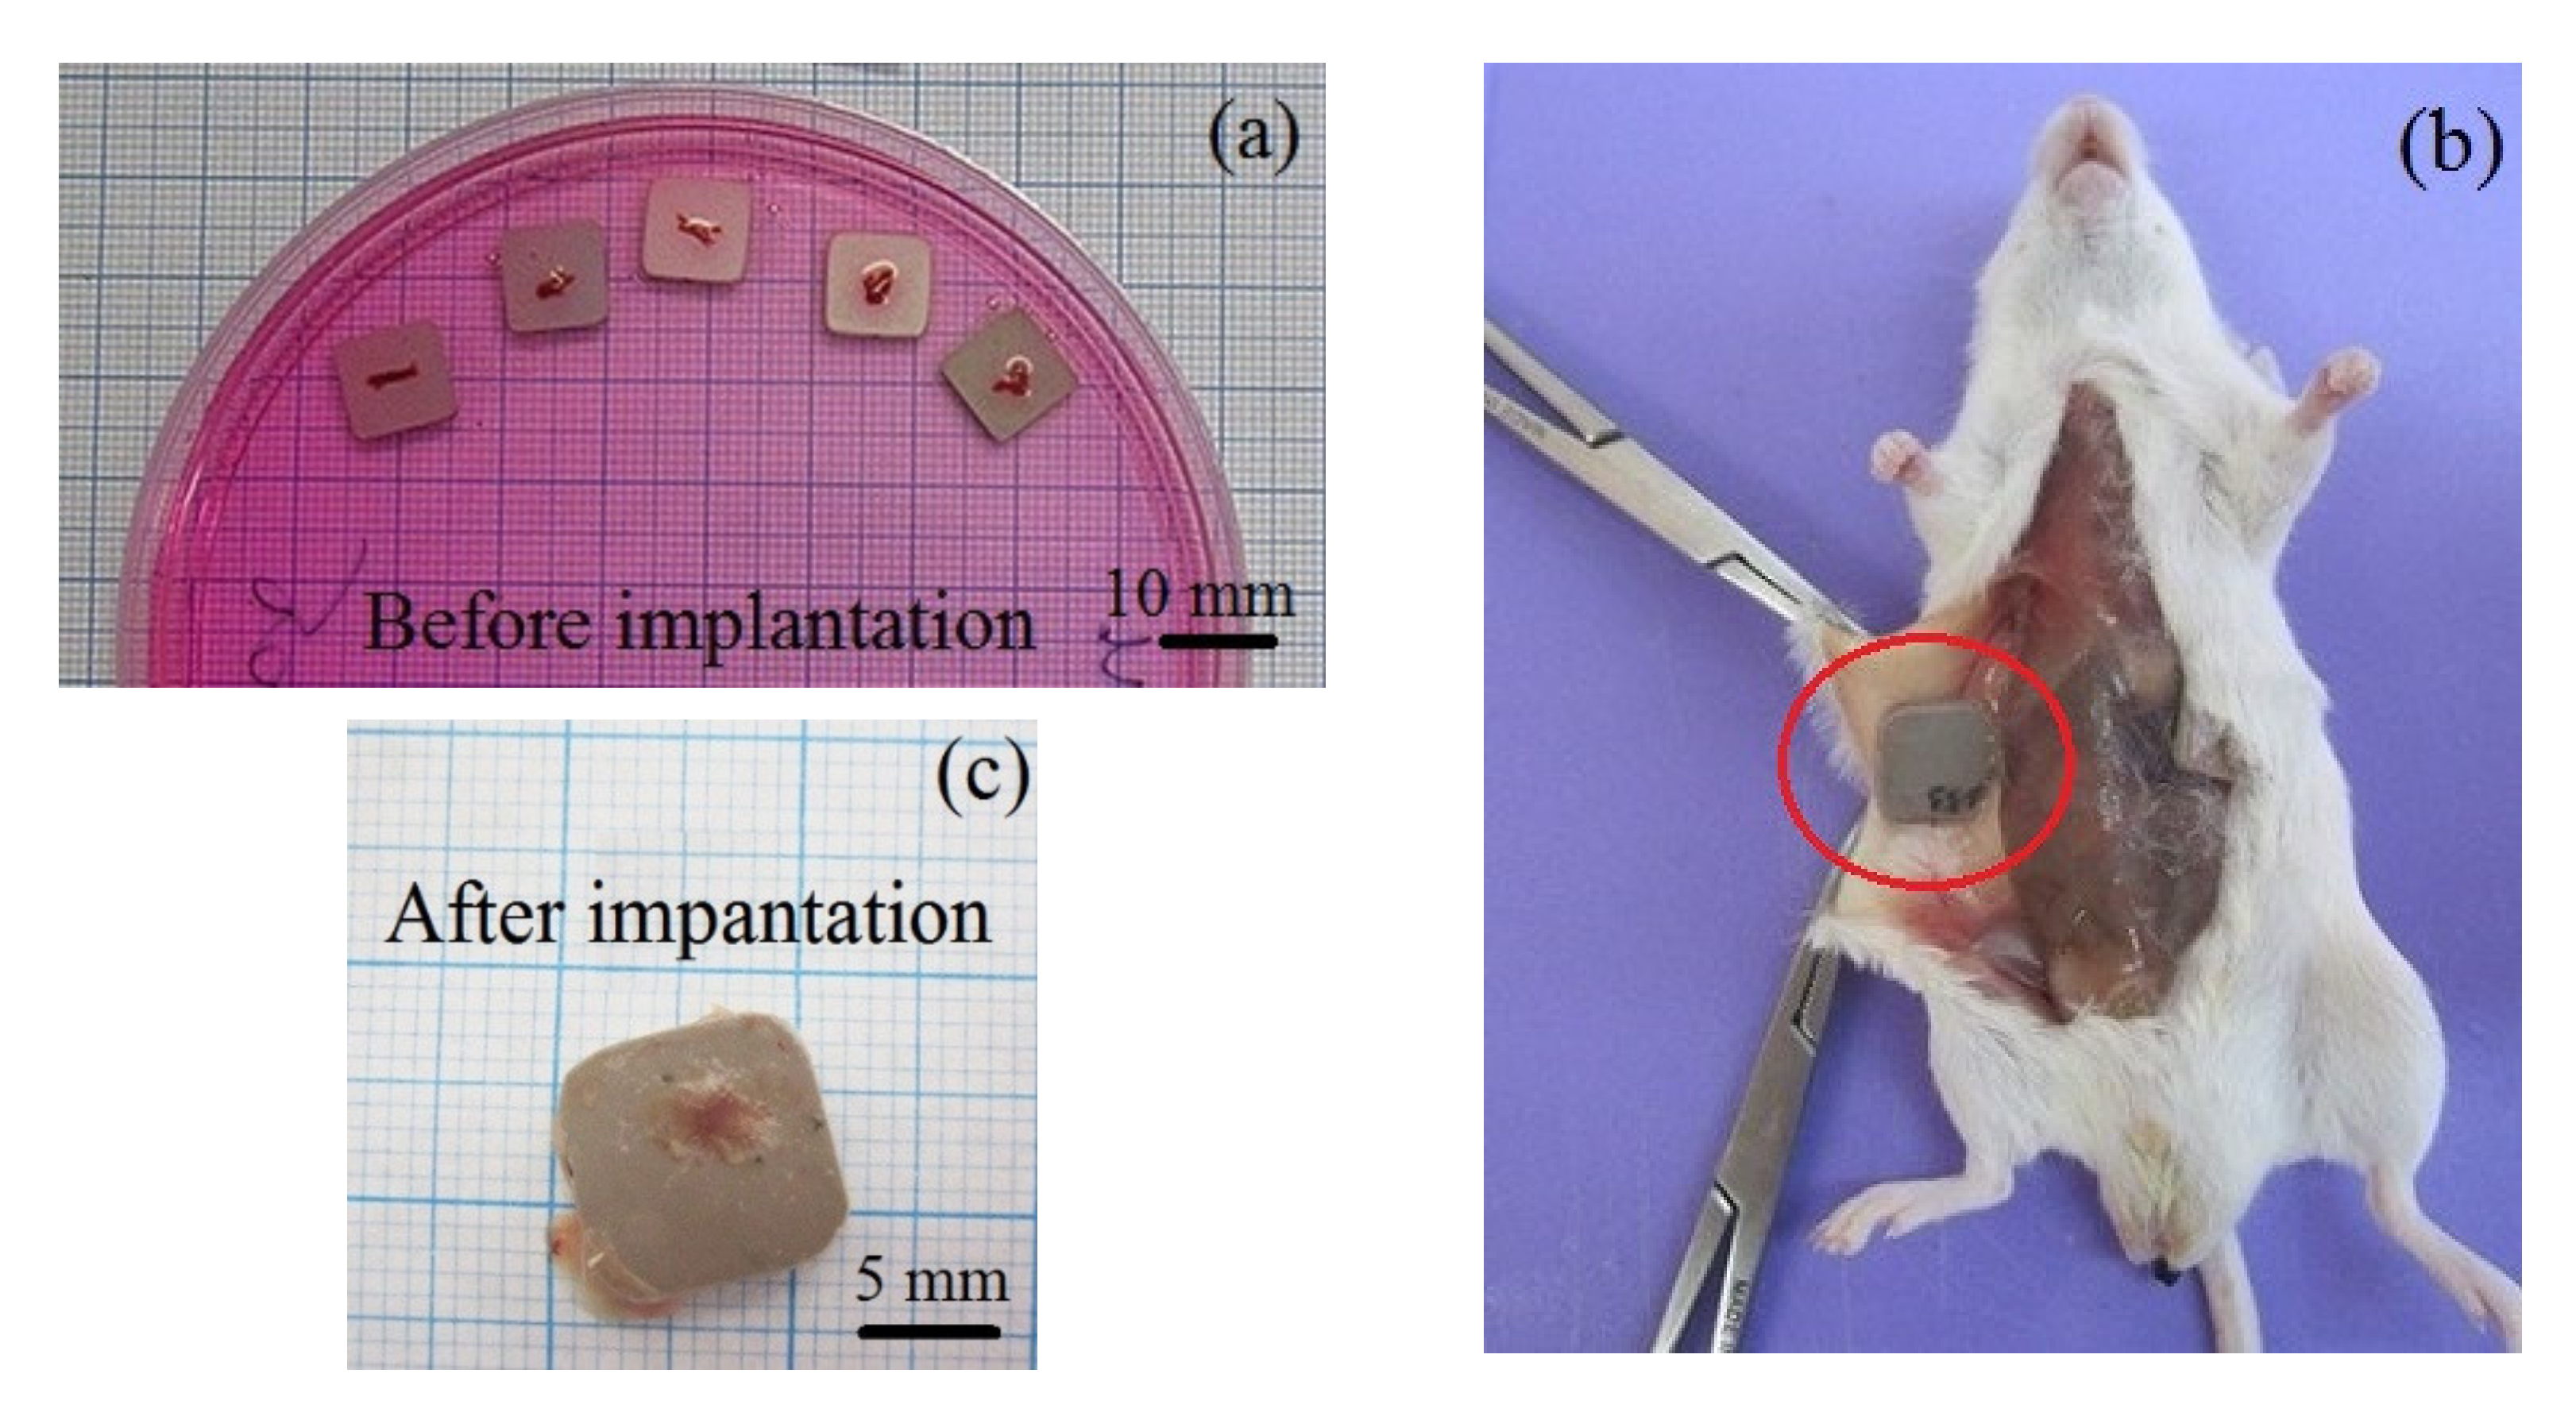

2.5. Ectopic Osteogenesis Test in Mice

3.4. Ectopic Osteogenesis in Mice

| Groups, n = 3 | Tissue lamellae Properties | ||

|---|---|---|---|

| Incidence of Tissue Lamellae, % | Incidence of Bone Formation, % | Histological Composition | |

| Ti substrate | |||

| CaP coating | 100 | 100 | Bone with marrow (Figure 8a); bone lamellae (Figure 8b). |

| Zn-CaP coating | 100 | 67 | Bone lamellae (Figure 8c); connective tissue ossification (Figure 8d); connective tissue (not shown). |

| Cu-CaP coating | 100 | 67 | Bone with marrow (Figure 8e); bone lamellae (Figure 8f); connective tissue (not shown). |

| Ti-40Nb substrate | |||

| CaP coating | 100 | 67 | Bone lamellae (Figure 9a); connective tissue ossification (Figure 9b); connective tissue (not shown). |

| Zn-CaP coating | 100 | 67 | Bone lamellae (Figure 9c); connective tissue ossification (Figure 9d); adipose, muscle and connective tissues (not shown). |

| Cu-CaP coating | 100 | 67 | Bone lamellae (Figure 9e); connective tissue ossification (Figure 9f); connective tissue (not shown). |